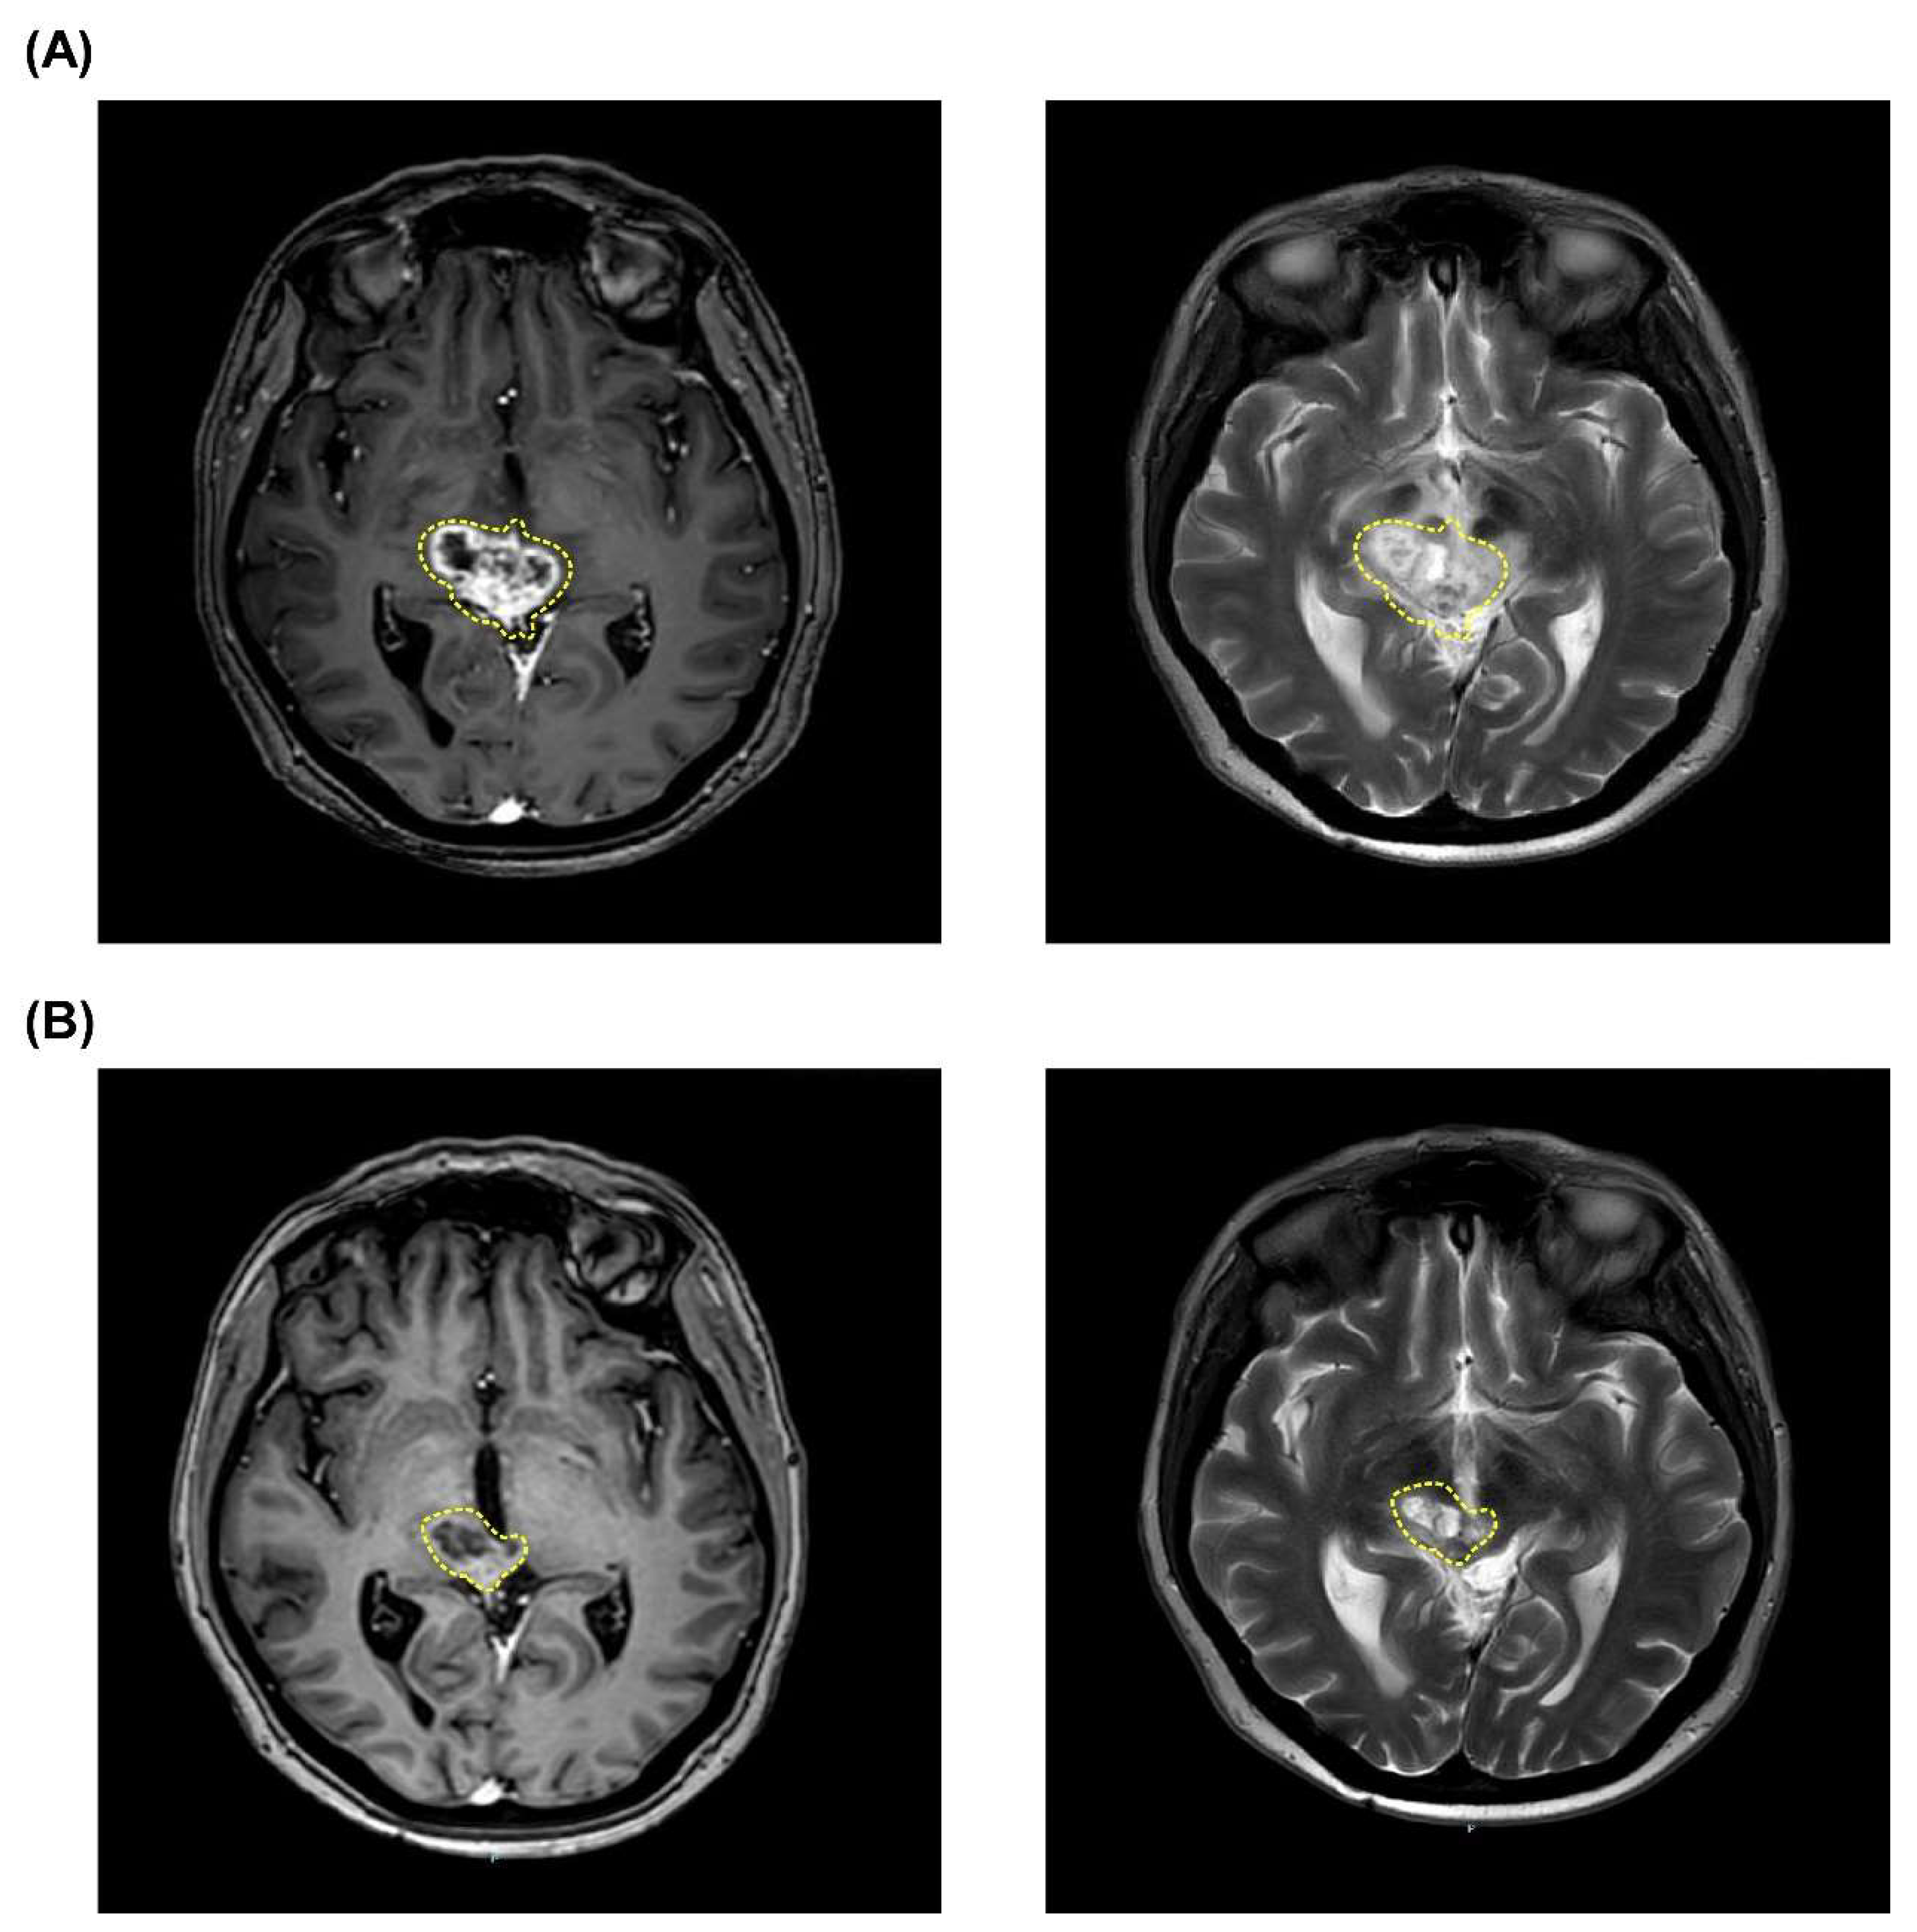

3.1.1. Case 1 (Patient #5)

| 5 | 6 | M | High-grade diffuse midline glioma | Diffuse | 70 | 8.77 | 2.45 | 5.53 | 24.19 | 7.22 | 4.19 | 11.54 | 2.11 | 2.11 | 24.62 | 5.76 | 3.38 | 9.40 | PR | Radiation necrosis † | Yes |